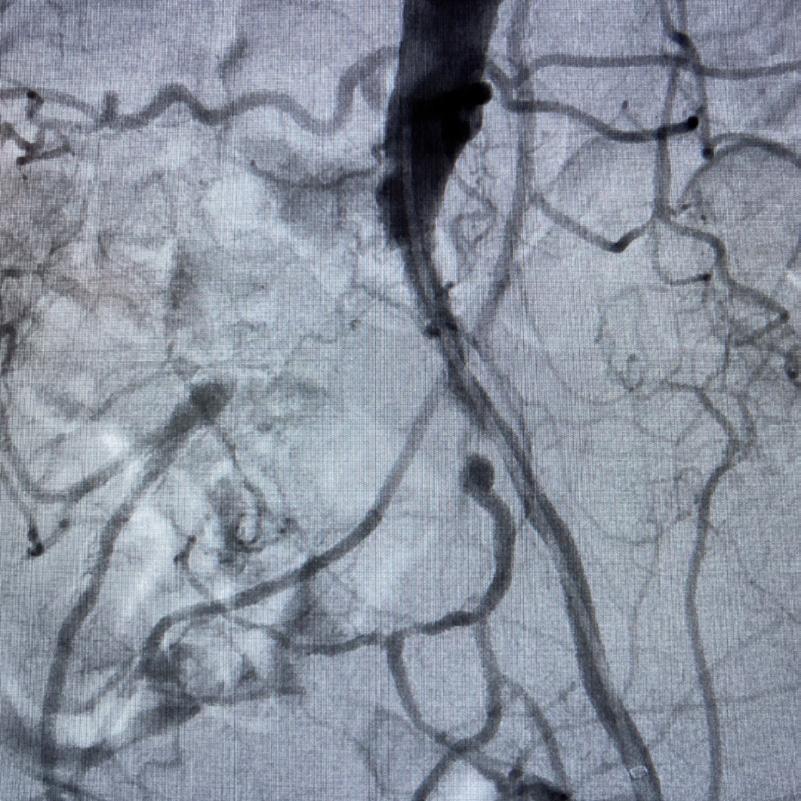

Case 1: The Shockwave L6 device in the setting of FEVAR and complex iliac stenosis

An 82-year-old man with a history of coronary artery disease (CAD), hypertension, hyperlipidemia, and peripheral arterial disease (PAD) presents with rest pain as well as

a large pararenal abdominal aortic aneurysm (AAA). His computed tomography angiography (CTA) revealed very dense and highly diseased iliac vessels with calcium deposition along most of the bilateral common iliac distribution.

The minimum luminal diameter (MLD) of the common iliac arteries measured roughly 4.5mm; however, the

“My experience with this system has taught me that appropriate balloon sizing is the single-most important predictor of a successful outcome”

healthy reference vessel diameter (RVD) was 9.5mm. He would require a fenestrated repair of the AAA along with complex iliac stenosis treatment, and extensive bilateral common femoral endarterectomies.

Further, we were concerned we would not be able to advance the 19F fenestrated graft. The endograft was prepared, and then both femoral arteries were exposed. We attempted delivery of the endograft via the right common iliac access. This failed. We then attempted delivery on the contralateral side. Despite multiple attempts, we made little progress. A 10x30mm Shockwave L 6 catheter was selected, and a total of 150 pulses were delivered to each iliac artery at just 4atm. This not only allowed for the delivery of our FEVAR graft but also the full unrestricted expansion of the endograft limbs in the common iliac arteries.

At the completion of the AAA, we took extra time to perform endarterectomies of the deep femoral arteries. His completion CT scan revealed a good seal of the AAA, patency of the renal fenestrations and unrestricted flow to the bilateral femoral arteries.

Figure 1. Pre-procdural CTA

Figure 4. Graft delivery